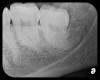

There are two specific types of DIDR sensor systems available to dentists in the marketplace: the hard-wired (HW) sensor and the photostimulable phosphor (PSP) sensor,1,2 also commonly known as phosphor "plates." A desirable feature common to both modalities is the ability to expose either bitewing (BW) or PA radiographic images. The BW radiograph (Figure 1) is usually considered more appropriate for caries detection, whereas the PA (Figure 2) is diagnostic for several different anatomic and pathologic issues.7

Fig 2. Left: PSP vertical PA radiograph of

maxillary bicuspid area demonstrating full root structure, several millimeters of bony anatomy beyond apices and maxillary sinus. Tooth No. 4 may be

traumatized as periodontal ligament is widened. Right: PSP horizontal PA radiograph of maxillary bicuspid area. Tooth No. 12 shows widened apical

periodontal ligament presumably caused by deep restorative filling. Some loss of supporting bone is evident interproximally, especially pronounced

between tooth Nos. 14 and 15.

Figure 2